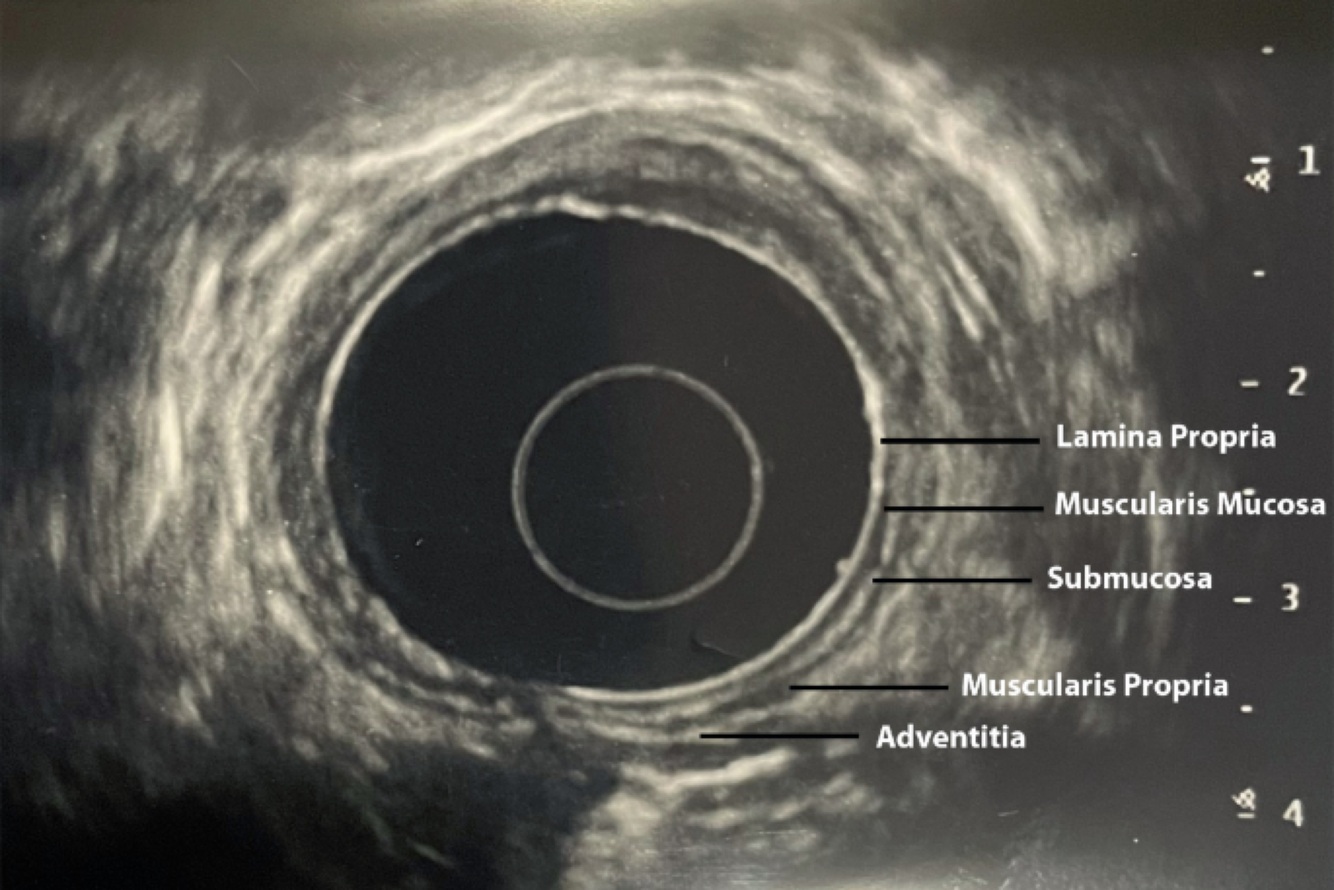

Layers seen on esophageal EUS

1st (hyperechoic) - epithelium/lamina propria

2nd (hypoechoic) - muscularis mucosa

3rd (hyperechoic) - submucosa

4th (hypoechoic) - muscularis propria

5th (hyperechoic) - paraesophageal tissue/adventitia

Muscle = dark (hypoechoic)